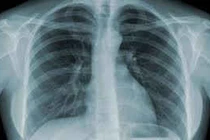

(khoahocdoisong.vn) - Phổi là một bộ phận quan trọng trong cơ thể với vai trò chính yếu là trao đổi các khí, đem ôxy từ không khí vào tĩnh mạch phổi, và điôxit cacbon từ động mạch phổi ra ngoài. Ngoài ra phổi cũng có một số khả năng như giúp chuyển hóa một vài chất sinh hóa, lọc một số độc tố trong máu. Dưới đây là những thực phẩm tốt nhất cho lá phổi.